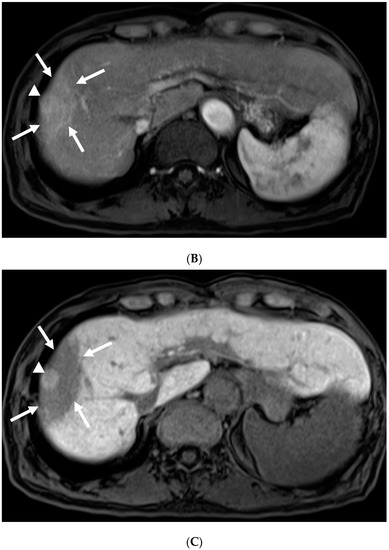

3.2. Imaging Follow-Up

3.4. Pathological Findings and Estimated Theory of FLR Mechanisms